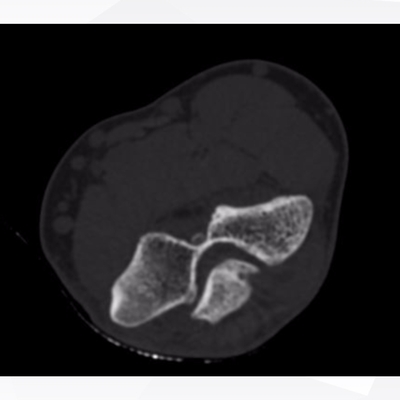

Click on an image below to view more info.